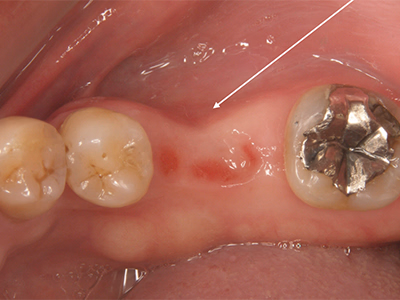

治療前後写真

治療前

治療後

他院で抜髄処置後も咬合時違和感が続く(破折リーマー残存の情報あり)

治療内容

- ① マイクロスコープ+ラバーダム下で再根管消毒

- ② CTで破折器具の位置・長さを確認し破折リーマー除去

- ③ 症状改善を確認し根管充填

- ④ ファイバーコア築造+セラミック装着

破折器具除去と無菌的消毒を徹底し、緊密充填と精密補綴を実施。長期経過で良好。